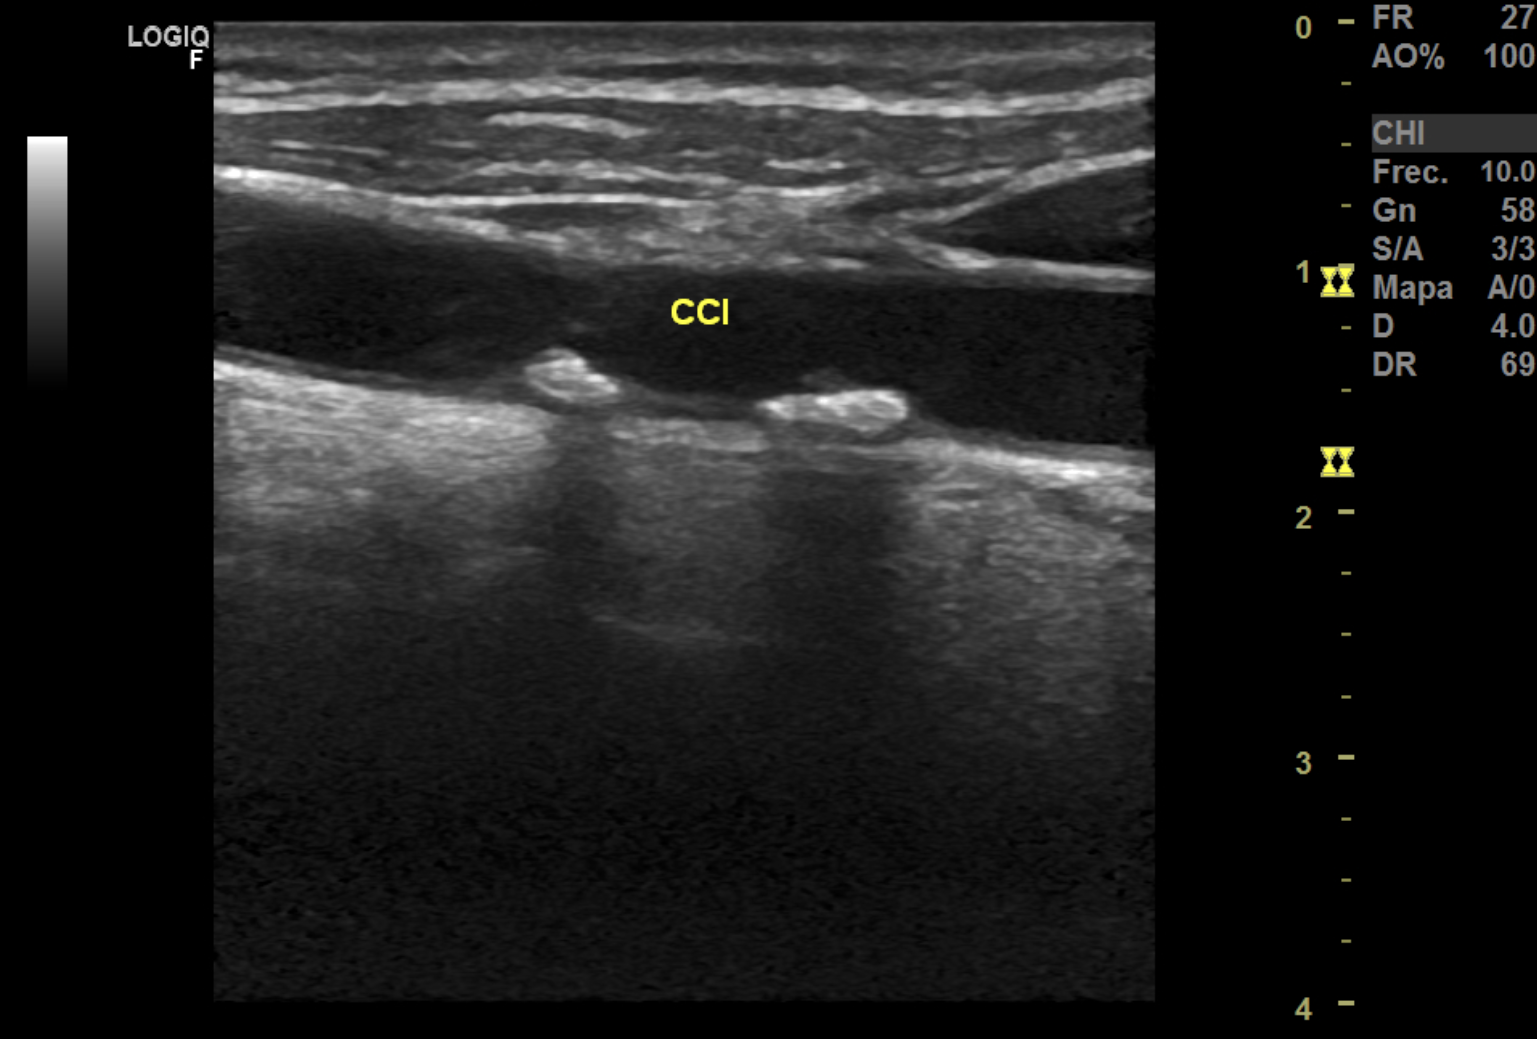

Hallazgos ecográficos

La ecografía Doppler carotídea realizada en AP mostró placas hiperecoicas y calcificadas en ambas carótidas comunes, con estenosis bilateral de aproximadamente 20% del lumen. Carótidas externas e internas permeables y morfología normal.